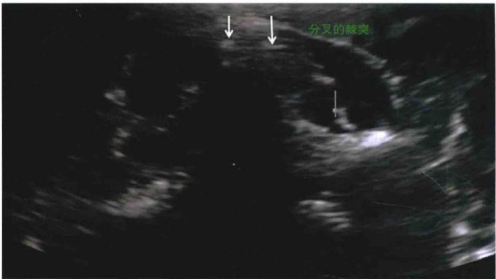

颈椎关节突关节是由颈椎的上关节突与上一椎体的下关节突在椎板和椎弓根交界处组成的关节。颈神经后支的内侧支在经过关节柱后部时发出关节支,一支支配上方的关节突关节(也称小关节),一支支配下方的关节突关节。因此,每一个颈椎关节突关节都有双重神经支配,也就是说每个关节接受2个节段的神经支配。C3颈神经后内侧支解剖与其他关节突关节有所不同,其深部内侧支绕过C3关节柱支配C3/4关节突关节,其浅表的内侧支被称作第三枕神经(TON),它从C2/3关节突关节侧方绕至后方发出关节支支配该关节。因此,只有C2/3的关节突关节被一个单独的TON支配。除了TON,其余后内侧支并不越过关节突关节的最高点,而是从前向后穿过两个关节间的最低点(如下图)。

图2:颈椎关节突关节与颈神经后内侧支示意图(此图片由倪勇老师提供)